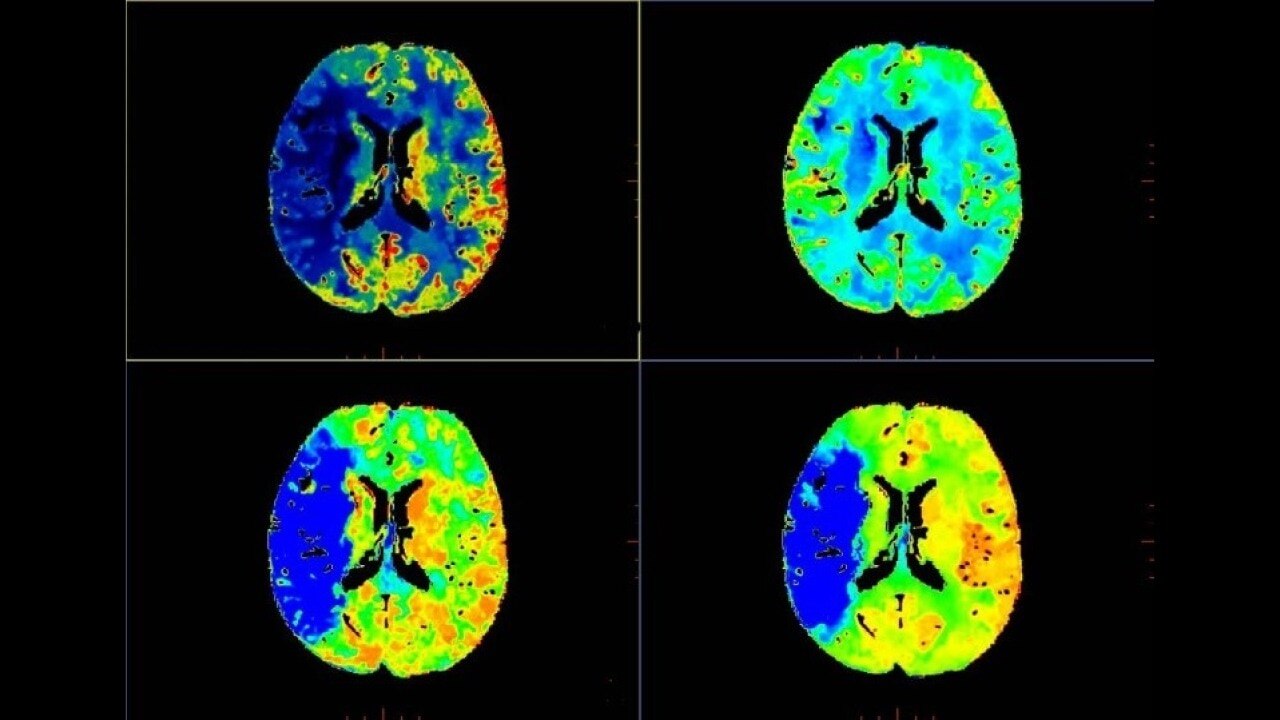

Brain perfusion

Easy-to-use automated workflow for CT stroke and tumor angiogenesis evaluation

Brain stroke protocol

• Automated generation of all functional maps: Blood Flow, Blood Volume, Mean Transit Time, and Transit Time to IRF Peak (Tmax)